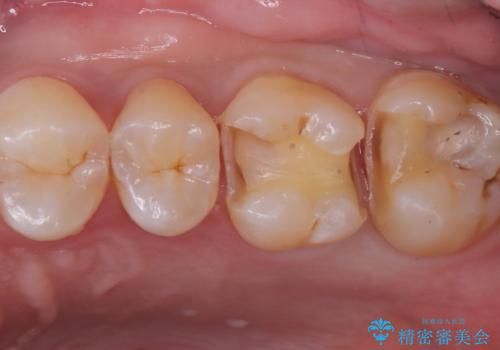

- 主訴:クリーニングと一緒に虫歯がないか確認してほしい

初診でいらした患者様で、口腔内を確認したところ左上6番目と7番目の歯の接する面を中心に両方の歯に虫歯が認められたため、セラミックインレーでの修復治療となりました。

左上6番の歯には元々修復物が入っていましたが、それも一度除去し新たにMOD窩洞のセラミックインレーをセットしました。